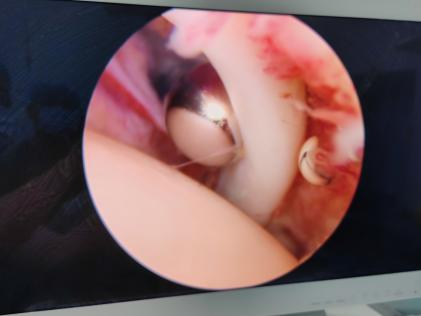

3. 术中探查。

4. 关节镜下关节囊松解、肩峰成形、单排铆钉改良Mason-Allen缝合。